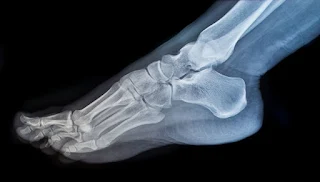

In Russia, they learned to decipher x-rays using artificial intelligence. The new program analyzes the results of the study and determines what the person is sick with. With it, lung cancer, breast cancer, tuberculosis, eye and blood diseases are already being diagnosed. Soon, the turn will reach the results of CT and MRI scans, writes News.ru.

Artificial intelligence was created by Russian specialists. This software automatically recognizes pathologies in a medical image without the participation of a doctor.

The main goal of the program is primary filtering of images, which will divide all the results into three groups: healthy people, people with a mild phase of the disease and severe patients. Using the program, doctors will have the opportunity to develop a plan for further work with the patient. For example, refer a patient to another hospital or schedule an additional examination.

However, artificial intelligence has no legal right to make a medical opinion. It will be issued by a radiologist and certified with a signature. The new system will only speed up and simplify the process of diagnosis.